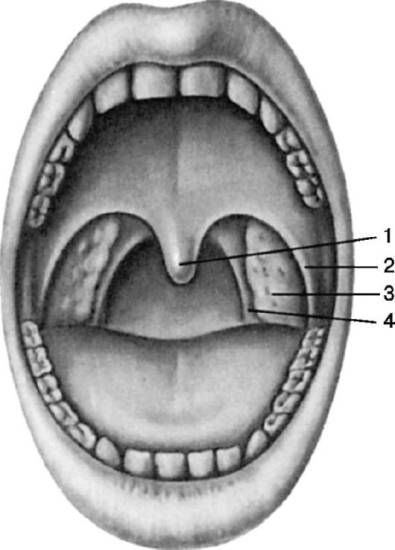

Во время визуального осмотра зева пациента определяется гиперемия (покраснение) гланд и стенок горла.

При непосредственном осмотре области миндалин визуализируется пленка беловато-желтовато-серого цвета. По внешнему виду она напоминает пятно от стеариновой свечки округлой формы. Пленка мягкая (по консистенции), окружена воспалительным (красным, отечным) ободком по краю и легко снимается ватным тампоном, после чего на его месте остается изъязвленная поверхность желтоватого цвета с ровными четкими контурами, которая кровоточит.

При наличии симптомов некротической ангины следует обязательно обратиться к врачу. В процессе обследования доктор может обнаружить на миндалинах:

- серый или желтый налет;

- язвы с неровными краями.